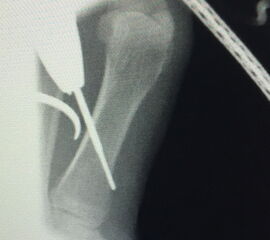

Liegt eine stark subduktische 5. Zehenposition vor, fräsen wir bevorzugt in der Kramertechnik für eine maximale Korrektur und Setzen für zwei bis drei Wochen einen intramedullären Draht nach proximal durch die Osteotomie (Abb. 27).

Abb. 27 a-d: Radiologische Darstellung intraoperativ (a) und vor dem Entfernen des Drahtes einer kompletten Schaftosteotomie mit intramedullärem Draht stabilisiert (b). Die Osteotomie wird minimalinvasiv durchgeführt und der Draht nach der Spülung über den gleichen Hautschnitt einfach in den Schaft hineingeschoben und die Osteotomie darüber stabilisiert. Das Köpfchen kann anschließend je nach Bedarf plantarisiert oder extendiert werden. Radiologische Verlaufskontrolle vor Entfernung des Drahtes (c-d).